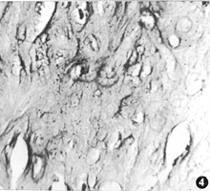

3.组织增生修复阶段:(1)内皮细胞层:AJV移植组在术后2周开始有内皮细胞自宿主动脉跨动-静脉交界处向移植静脉管腔生长,同时残存于静脉内表面的内皮细胞开始增殖并向四周延伸;HUV移植组在术后1个月才有内皮细胞跨动-静脉交界处向移植段管腔生长。术后3个月两组静脉的内表面大部分区域均已为内皮细胞覆盖,但中央仍缺乏内皮细胞,AJV组较HUV组的内皮细胞生长快一些。移植后6个月,新生内皮细胞已完全覆盖于两组静脉的内表面,这些内皮细胞排列整齐,细胞无裂隙(图2),说明整个移植段已基本内皮细胞化。(2)内皮下层:裸露的内皮下层血液成分沉积逐渐减少,代之以成纤维细胞、胶原纤维增生,这就构成了新内膜的成分。随着时间的延长,新内膜的多细胞层结构越明显,多达10层。AJV组在术后2周,HUV组在术后1个月移植静脉距吻合口附近内皮下层可见有肌内膜细胞,至术后3个月移植段中央的内膜下亦见有散在的肌内膜细胞(图3),术后6个月内皮下已由纤维结缔组织和散在片状的软骨样化生所代替(图4)。(3)中膜和外膜:中膜内平滑肌细胞增生,部分出现肌内膜细胞样变,并逐渐移向内膜下。外膜中的滋养血管增多,成纤维细胞增生活跃,术后3个月开始,外膜中纤维结缔组织逐渐增多。

图4 HUV移植段内膜软骨样化生 HE×450